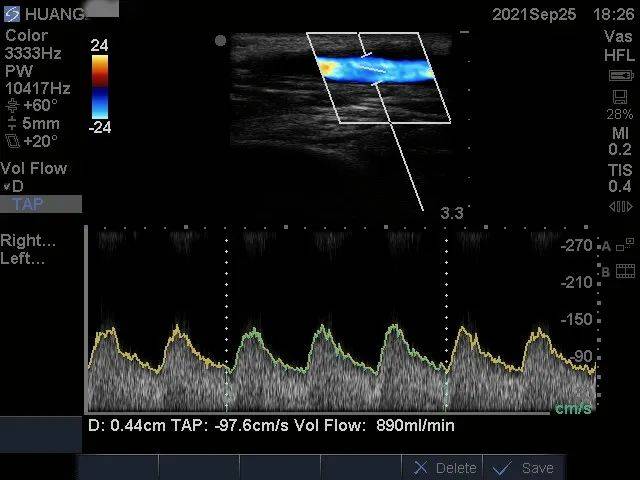

术后彩超示:吻合口狭窄消失 , 上肢人工血管动静脉内瘘通畅 , 震颤及杂音良好 , 测血流量890ml/min(图3) 。

图3:术后血流量